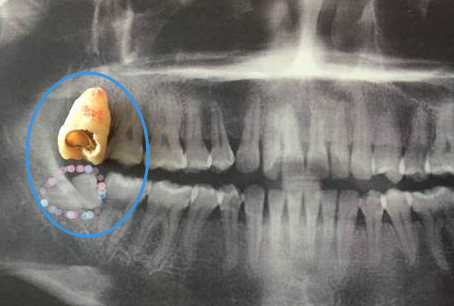

4、還有,右側(ce) 下頜智齒造成自身蛀牙,也需要拔除智齒後,否則可能會(hui) 引起鄰牙也蛀牙。